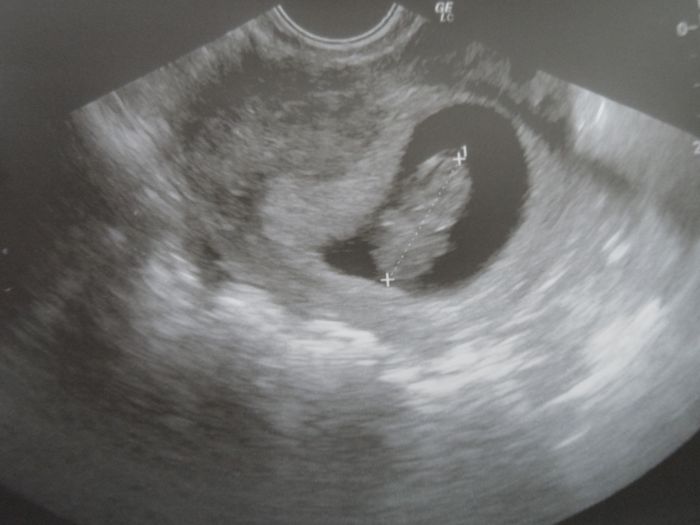

takže tady vám představuju našeho andílka(přítel říkal,že vypadá jak gumový medvídek)

Ahojky, Denis gratuluju ke kontrole, fotecka kraasna

Holky krásné fotečky! Přeju ať vše probíhá bez komplikací i nadále

Deni goúmový medvídek je super

Deniss nádherná fotečka!!!